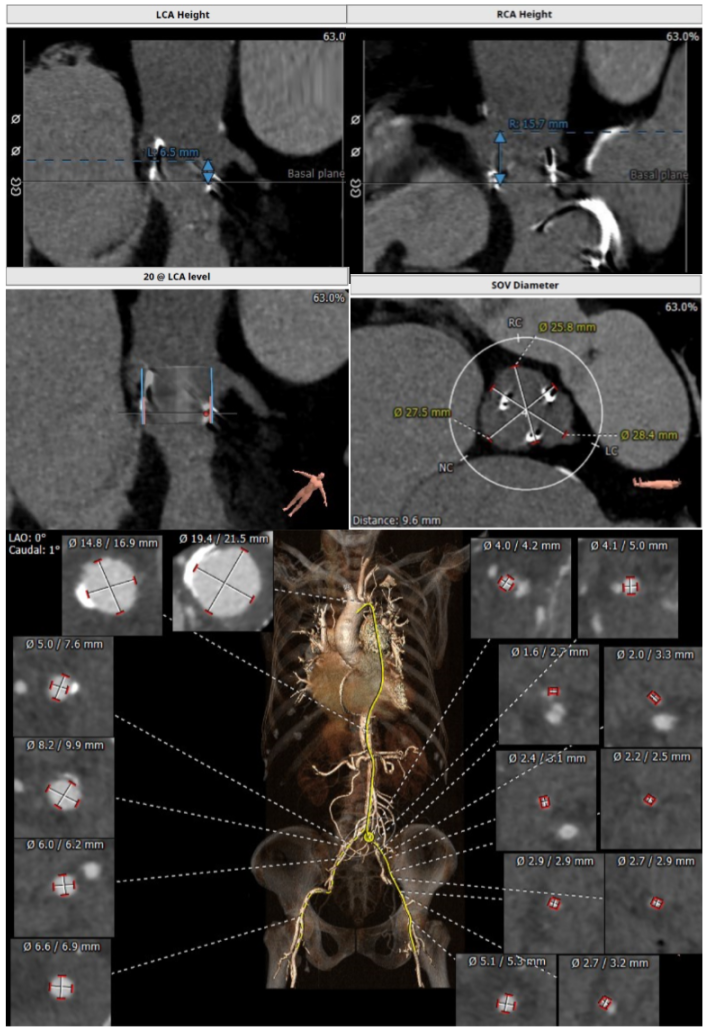

主瓣瓣中瓣CT评估

二尖瓣瓣中瓣CT评估

经过充分的术前食道超声及心脏CTA的评估,团队一致选择目前国际上瓣中瓣(Valve in Valve)技术使用最多最成熟的器械——Edwards SAPIEN3瓣膜。与林阿姨及其家属充分沟通后,在经验丰富的王焱院长的指导下,珠海市人民医院结构性心脏病团队决定为林阿姨同期进行主动脉瓣及二尖瓣的双瓣膜置换,采用的方案是先经股动脉途径为其行主动脉瓣的瓣中瓣植入(VinV TAVR),然后经股静脉途径,穿刺房间隔后,行二尖瓣的瓣中瓣植入(VinV TMVR),视情况对房间隔穿刺后的缺损进行封堵。